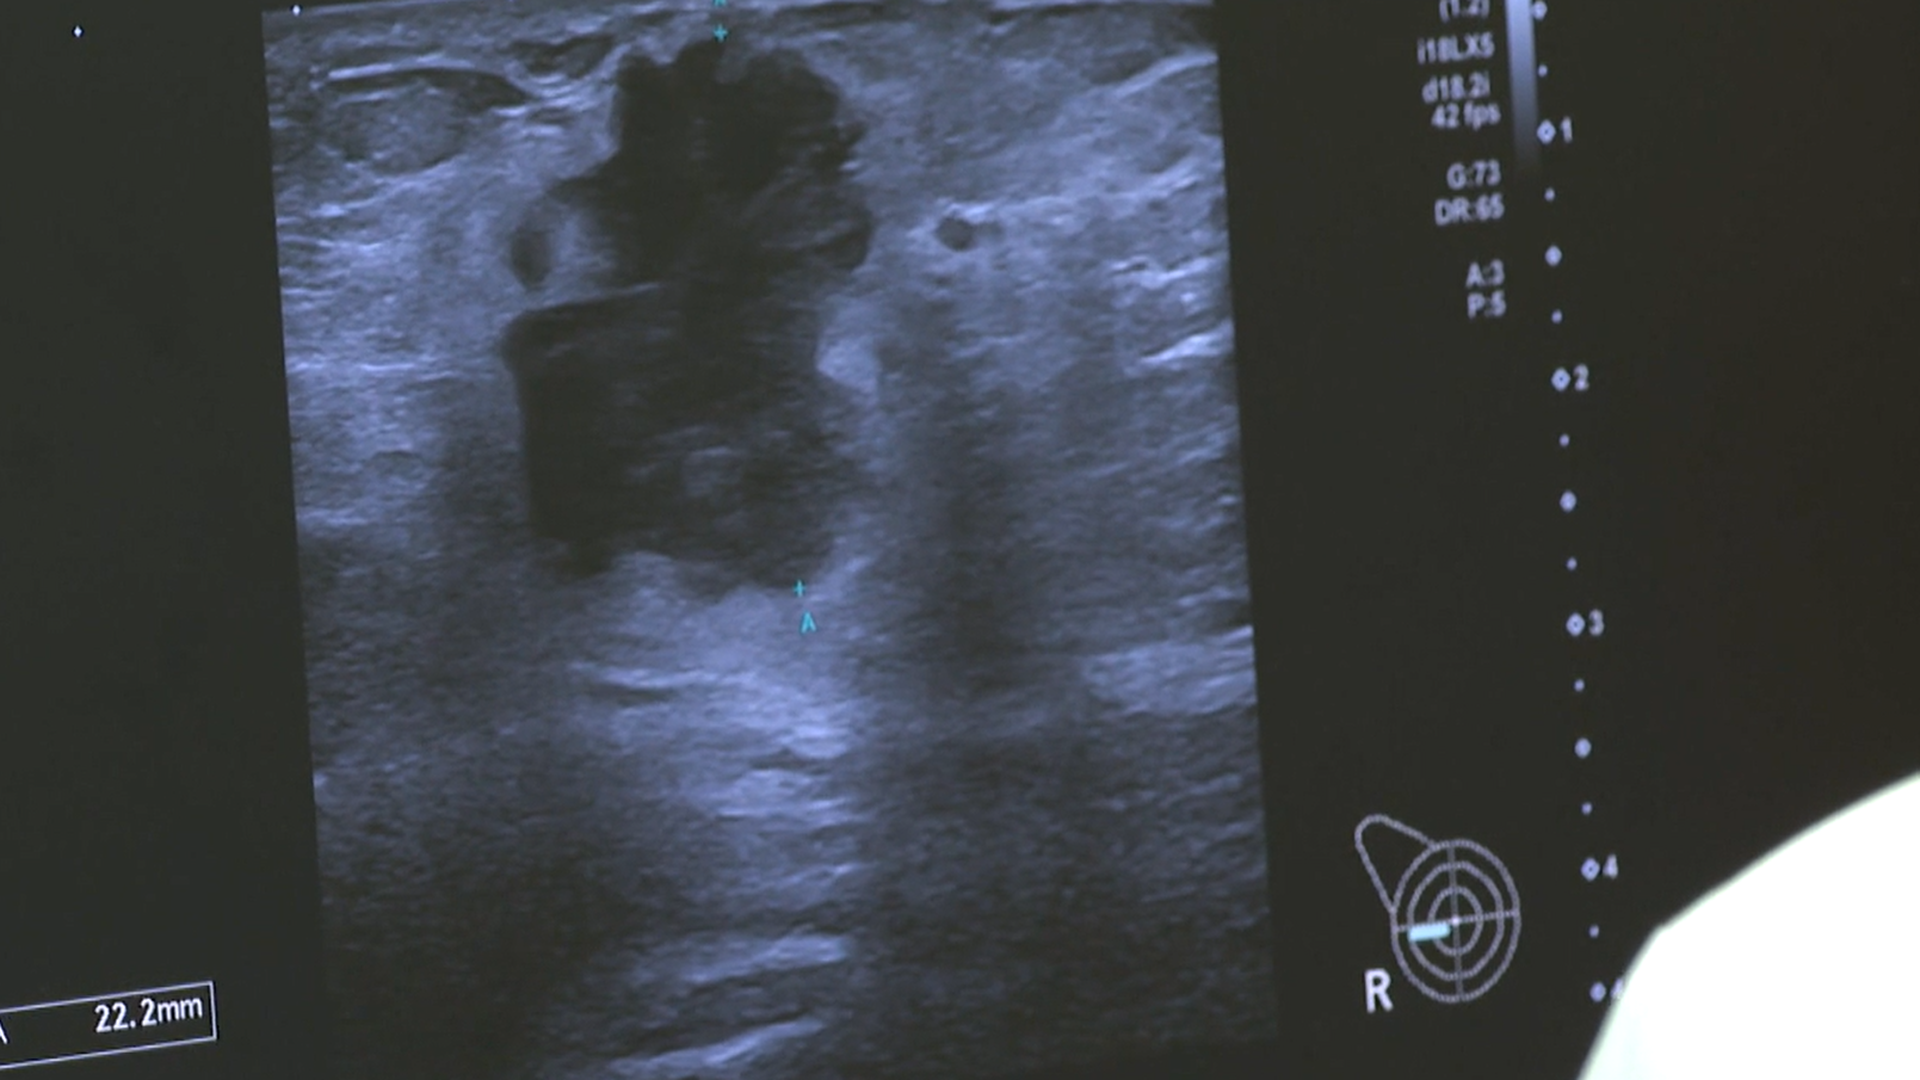

“Me dijeron que tenía un cáncer en estadio tres”, asegura. Su caso se suma al de cerca de 2.000 mujeres. "El fallo fundamentalmente está en las listas de espera para la ecografía de mama", advierte Miguel Ángel Montilla, médico del Hospital Virgen del Rocío.